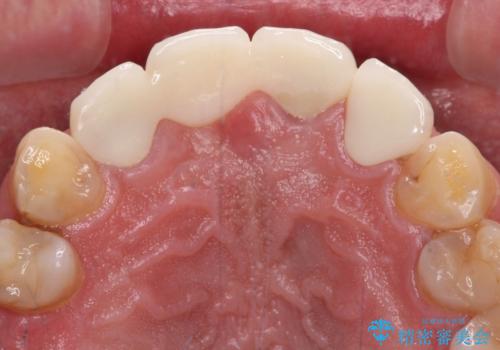

歯肉移植や根管治療終了後、オールセラミッククラウンおよびブリッジにて補綴することとしました。

歯の幅径のバランスが取れ、自然な口元となりました。